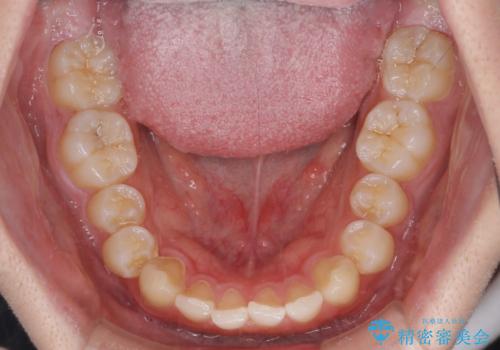

- 前方に傾斜した前歯を気にして来院された患者様です。

強く食いしばってしまう癖があり、下顎前歯に押し出されて上顎前歯が前方へ斜めに突き出している状態でした。

IPR(歯と歯の間を削る)を多用して、インビザラインにて矯正治療を行うこととしました。

口元を引っ込めるためのゴムかけを頑張っていただき、満足のいく上顎前歯の傾斜へ改善することができました。